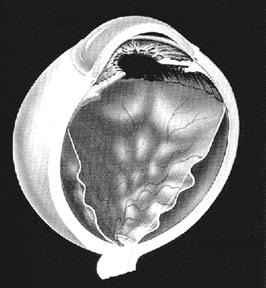

Decolarea de retina reprezinta separarea celor doua straturi embrionare ale retinei (epiteliul pigmentar si neuroepiteliul) intre care nu exista jonctiuni celulare. Acest spatiu virtual este un vestigiu al cavitatii centrale a veziculei optice; se vorbeste de decolare de retina atunci cand acest spatiu devine real, dar de fapt asa cum am aratat este vorba numai de decolarea neuroepiteliului, cu dedublarea retinei (Fig. 17.8)

Fig. 17.8 - Decolare de

retina - aspect schematic